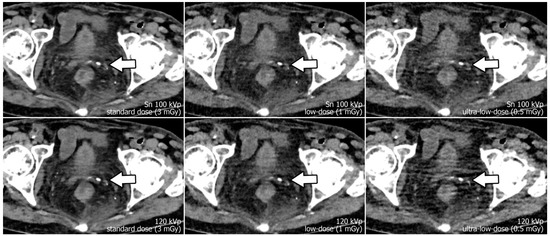

Reconstruction of datasets followed identical parameters: slice thickness and increment were set to 3 mm each, and the field of view to 400 mm with a 512 × 512 pixel matrix. A soft tissue convolution kernel (Br36) was applied with the highest strength level of a dedicated quantum iterative reconstruction algorithm (QIR 4). For polychromatic scans, “T3D” mode was enabled, which includes photon energies between 20 and 120 keV [29]. Window settings were pre-set to 300/40 Hounsfield units (width/center) were employed for dedicated analysis of soft tissue. However, readers were given the possibility to adjust these settings at will during image quality assessment. Examples regarding differences in image quality of the pelvic region between acquisition protocols are provided in Figure 1, while Figure 2 illustrates the encumbered demarcability of the lower Ureter in ultra-low-dose scans.

Figure 1.

Axial view of the left distal ureter (arrow). Note the impaired image quality due to hypodense streak artifacts in polychromatic scans at 120 kVp (lower row), especially with ultra-low radiation dose. (The arrow marks the left ureter with an adjacent phlebolite.)